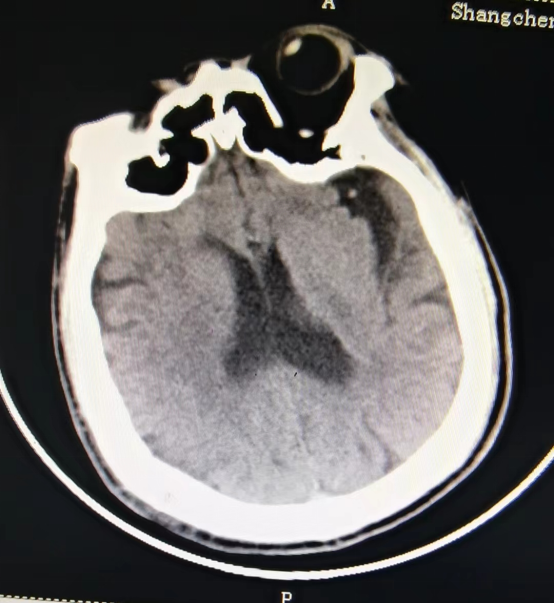

近日,55岁的冯先生突发急性脑梗死,我院卒中中心启动绿色通道,给予静脉溶栓桥接取栓治疗,成功打通堵塞的“生命管道”,患者转危为安,术后恢复良好,避免了“一人中风,全家瘫痪”的悲剧。

冯先生的成功救治,是静脉溶栓桥接动脉取栓治疗的完美结合。这次抢救工作的完美收官依靠的绝不仅仅是个人能力,它是整个团队共同努力的结果,检验了我院卒中中心对于脑卒中患者的快速鉴别诊断及多学科协作救治能力。我院卒中中心就是这样一支这样技术精湛、素质过硬的团队,在卒中介入治疗领域已经具备较强的综合实力,他们始终秉持着时间就是大脑、时间就是生命的理念,不断优化卒中急救模式和流程,为保障大别山区卒中患者能够得到及时、规范、有效的救治,降低县域卒中死亡率、致残率而不懈努力,为助力全面建设健康中国贡献自己的力量。